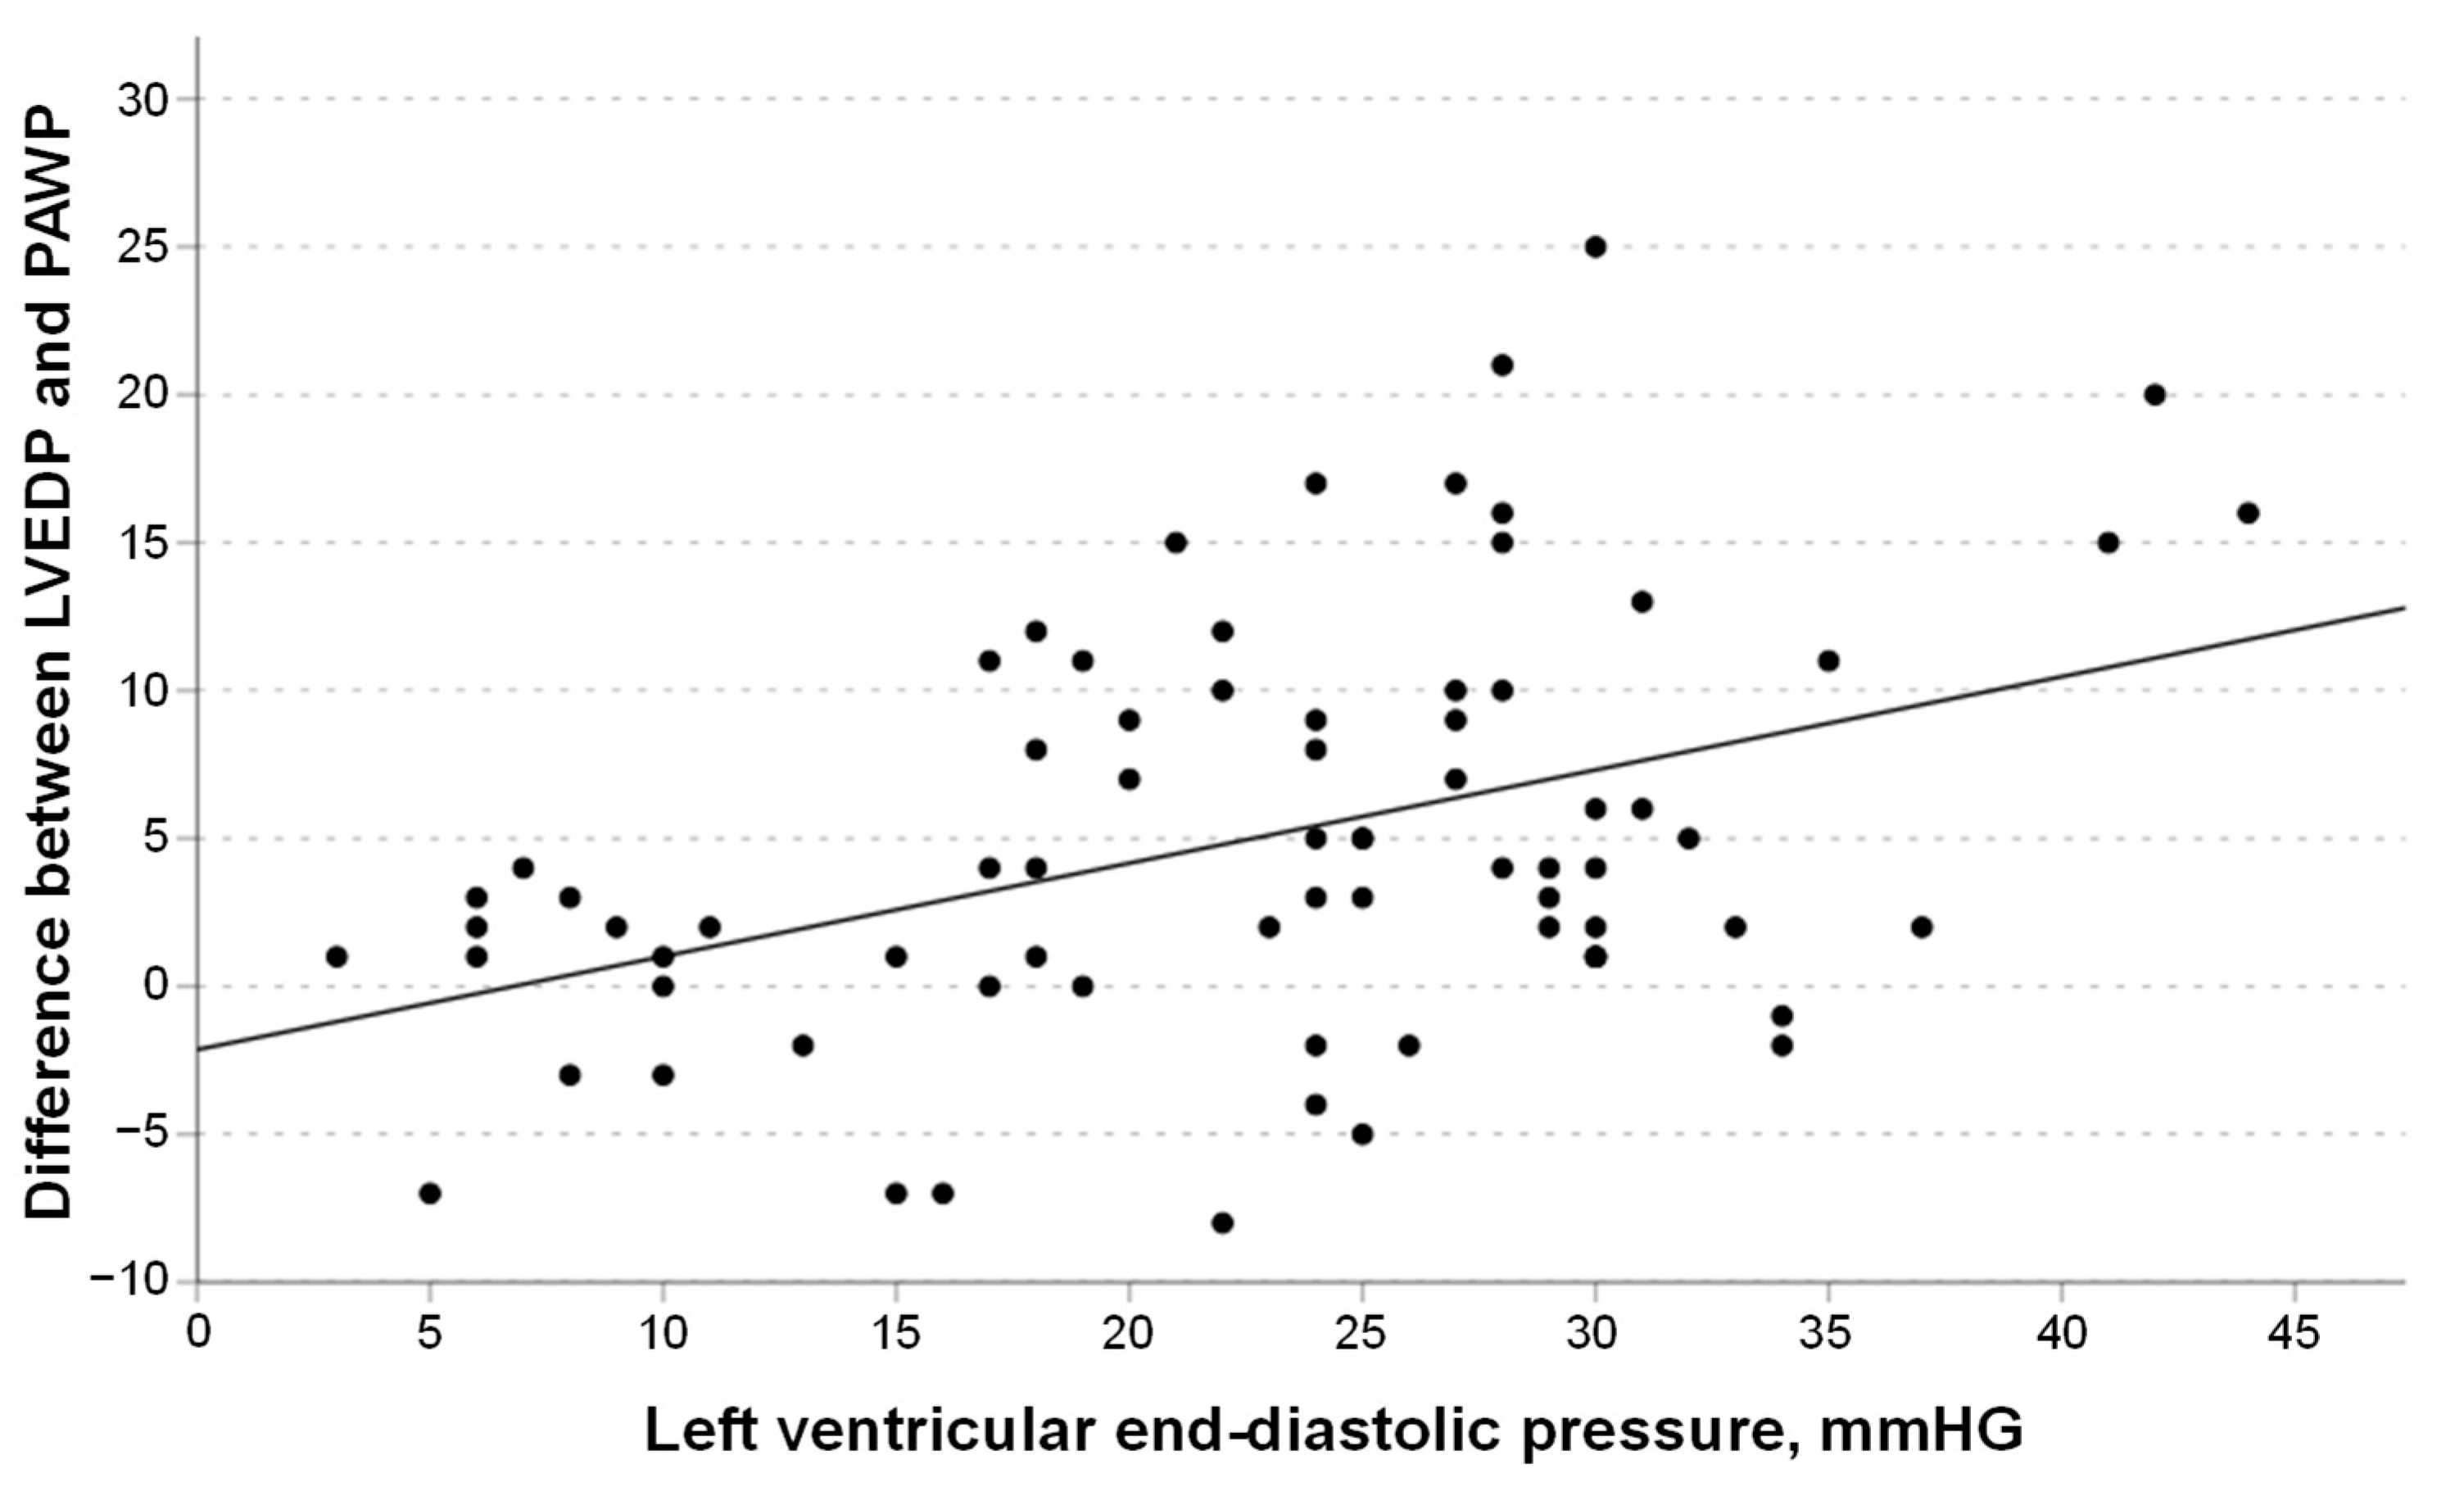

3.3. Correlation of PAWP with LVEDP

3.4. Linear Regression Models

3.5. Characteristics of Patients with Elevated LVEDP